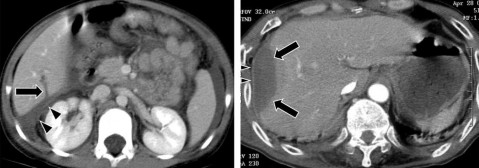

Hình 1.21. CTG độ V. Rách nhu mô gan thùy gan P và thùy gan T.

Hình 1.22. CTG độ V. Vết rách gan sâu, tổn thương vào các TM gan.

Nguồn: Shanmuganathan K, Mirvis SE [21].

Theo một số tác giả, tỷ lệ CTG độ I là 1,2 – 35,8%; độ II là 18,1 – 27,3%; độ III là 21,6 – 44,0%; độ IV là 10,8 – 28,3%; độ V là 4,5 – 8,4% [2, 7, 34].